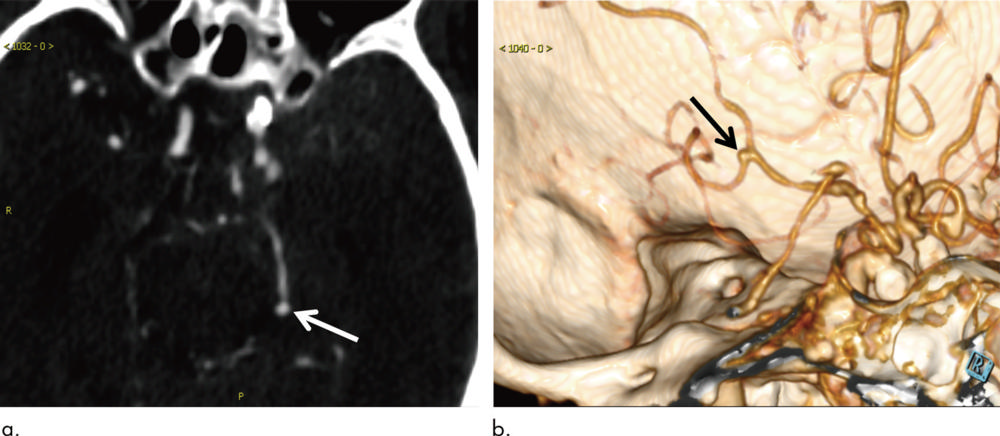

Figure 4. Images in a 54-year-old woman with aneurysm 2.9 mm in maximum diameter located on left internal carotid artery (arrow). (a) Axial section head CT angiogram and (b) volume-rendered three-dimensional reconstruction image. Aneurysm was missed by algorithm, possibly because of small size (<3 mm) and location near skull base bone.